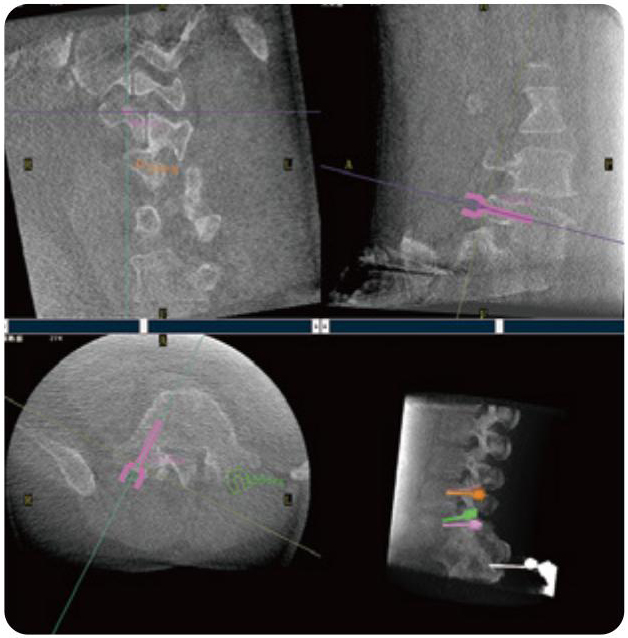

Clinical picture

临床图片